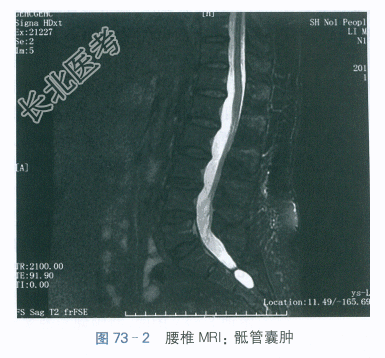

腰椎MRI:腰椎退行性变,L₄/L₅椎间盘膨出,骶管囊肿。如图73-1、图73-2所示。

患者,女,61岁,因“左臀部痛伴左下肢放射痛1月”就诊。患者1月前不慎在浴室滑倒,当时左臀部着地,后出现左臀部疼痛伴左下肢放射性痛,呈阵发性刺痛,影响睡眠,无行走困难,经刮痧、贴膏药治疗后无明显缓解。腰椎MRI示“腰椎退行性变,L₄/L₅椎间盘膨出,骶管囊肿”。现为求进一步诊治,拟“梨状肌综合征”收治入院。发病以来患者精神可,饮食可,睡眠稍差,二便无殊,近期无明显体重变化。